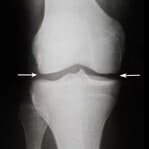

Siente la diferencia

desde los primeros días de uso

-

Primera aplicación

Antes

Antes  Después

Después - el dolor se va

- la inflamación disminuye

- el enrojecimiento desaparece

-

1 semana

Antes

Antes  Después

Después - el dolor desaparece al caminar y levantar objetos pesados

- la piel recupera su color saludable

- los tejidos se vuelven más elásticos

-

1 mes

Antes

Antes  Después

Después - la movilidad articular se restaura por completo

- las paredes vasculares se fortalecen

- el resultado dura mucho tiempo